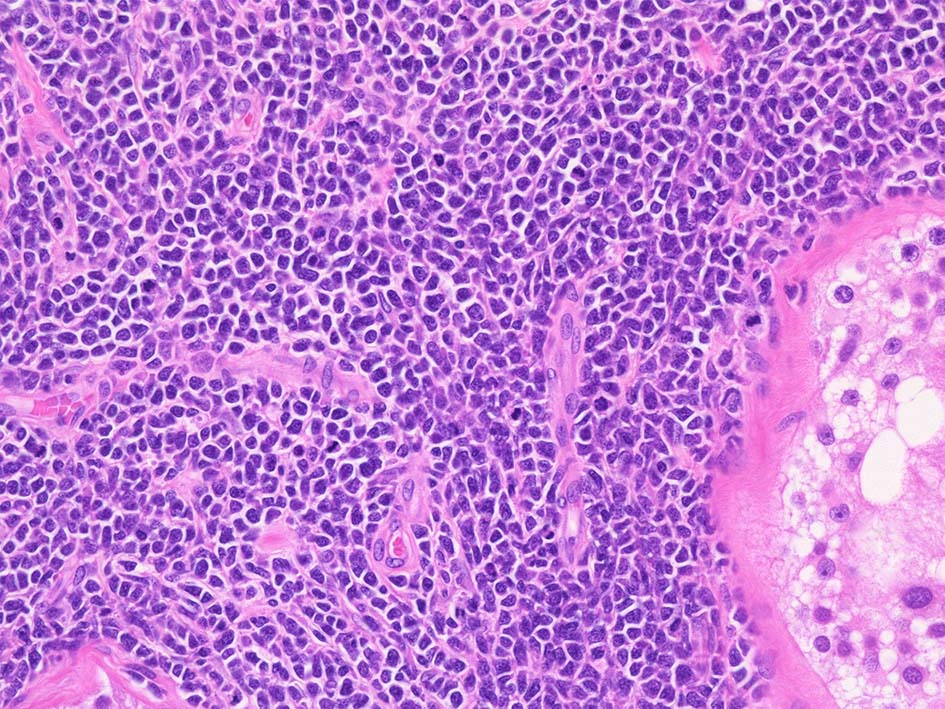

精細管の多くがスペアされ, 間質にlymphoid cellsが密に浸潤している. わずかな精細管に浸潤が認められ萎縮や破壊像が認められる. 精細管において Lymphoepithelial lesion(LEL)に似た所見がある.

類円形/多稜形の核をもつN/C比大の細胞. 粗大なクロマチンが増加, 核小体は不明瞭. DLBCLに認められるcentroblasts/ immunoblastsの細胞所見と異なる.